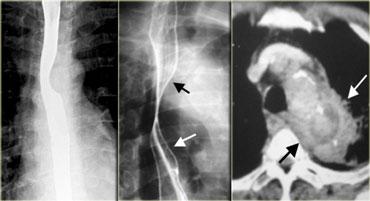

Bên trái là hình ảnh một bệnh nhân mắc hội chứng Boerhaave.

Chụp thực quản barium cho thấy khí ngoài lòng thực quản (mũi tên) mà không có thuốc cản quang thoát ra ngoài.

CT cho thấy khí ngoài lòng thực quản (các mũi tên).

Vết rách ở thực quản đoạn xa bên trái được xác nhận trong phẫu thuật.

CT có thể phát hiện lượng nhỏ khí ngoài lòng thực quản hoặc thoát thuốc cản quang mà không thể nhìn thấy trên X-quang hoặc chụp thực quản cản quang.